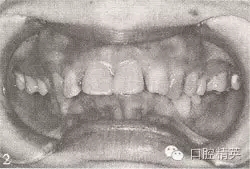

參見圖9-33 雙側(cè)后牙鎖頜矯治前后

A.雙側(cè)后牙鎖頜矯治前

B.雙側(cè)后牙鎖頜矯治后